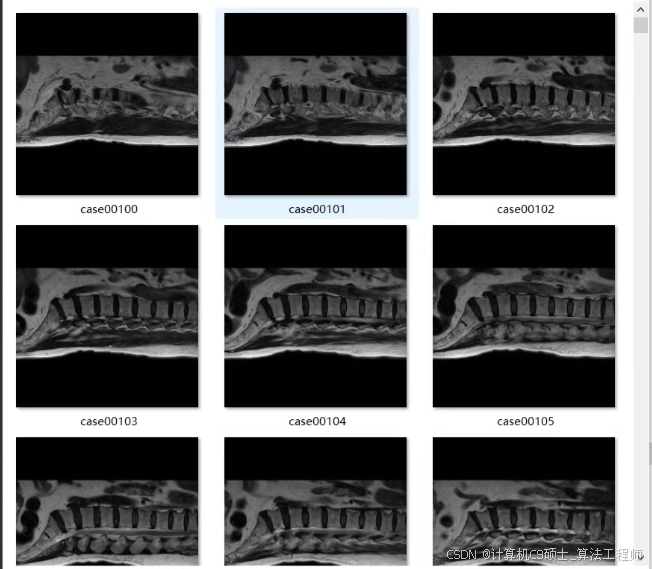

包含脊椎分割数据集:

原图,标签分别2460张

原图,标签分别2460张在这里插入图片描述